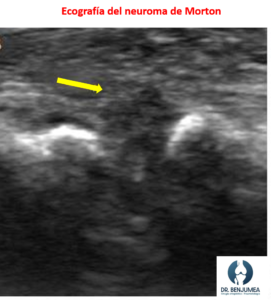

El neuroma de morton puede confundirse con una metatarsalgia por otra causa. La consulta con un traumatólogo puede ayudar a saber si el dolor es causado por un neuroma de morton. Lo habitual es realizar una exploración física. El neuroma de morton suele acompañarse de entumecimiento o sensaciones de calambre y hormigueos en el 3er y 4to dedos del pie. Además, hay pruebas como la ecografía o la resonancia magnética que nos darán ayuda al diagnóstico. El estudio de la pisada puede ayudar a diferenciar una causa de otra.

- Infiltraciones: Las infiltraciones pueden estar indicadas para ayudar a disminuir el dolor. Es muy efectivo realizar las infiltraciones bajo control ecográfico para dirigir el fármaco exactamente a la zona de irritación. Por lo general se suele emplear corticoides

- Cirugía mini-invasiva ecoguiada: es una cirugía que se realiza con una incisión muy pequeña, generalmente se indica cuando buscamos descomprimir el nervio sin quitar la tumoración, es decir, retirar la causa que provoca la irritación del nervio. La ventaja de esta cirugía es que se realiza con una incisión de menos de 1 cm bajo control ecográfico, con lo que se disminuye el riesgo de lesión de otras estructuras.